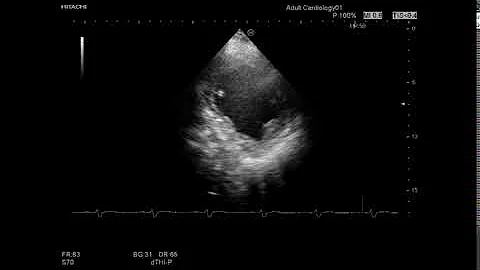

Case 390 Echo Left Bundle Branch Block Lbbb

2018 0:21